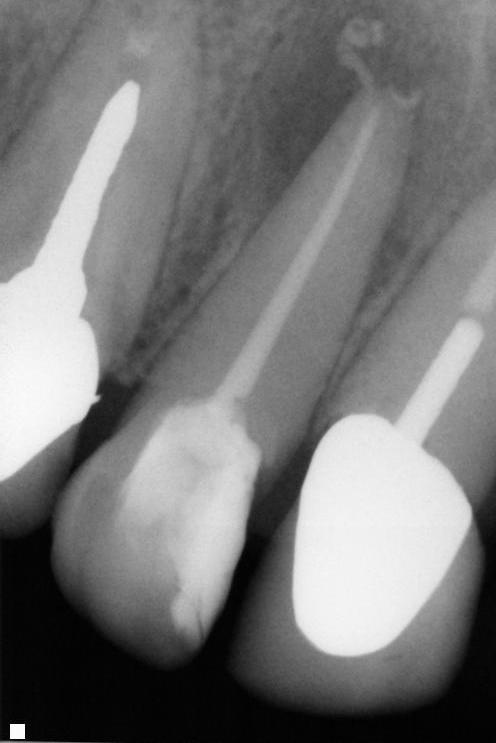

This is the X ray of the tooth that the patients previous dentist said was unrestorable. The patient was offered an extraction. However he patient wasn't yet ready to loose his front tooth and decided to seek out another opinion. After a bit of an internet search he arrived at No9.

We had a chat and took the picture above which confirms that there is almost no root canal present and therefore the tooth is almost impossible to restore. However, with time, skill and a good bit of determination it is often possible to get down these impossible canals, and save the tooth.

And here we have the finished result.